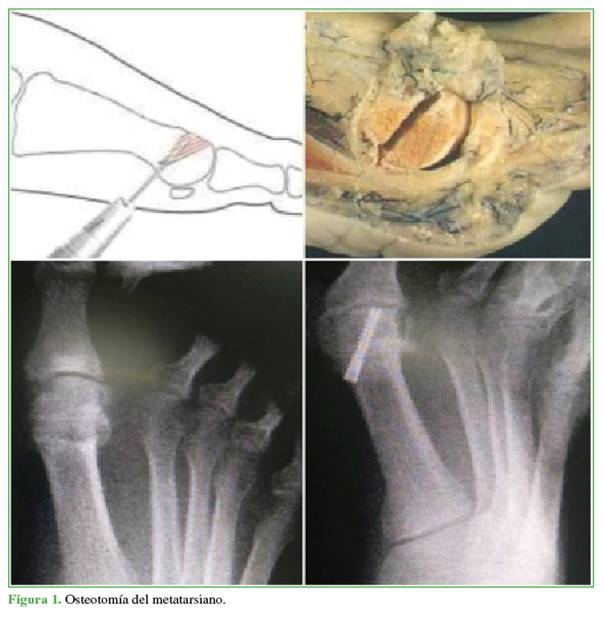

Osteotomía distal del primer metatarsiano. Por el mismo portal percutáneo previo, se realiza una osteotomía en cuña dorsal con fresa tipo Shannon larga; se procede al cierre mediante osteoclasia y se fija con tornillo de compresión, de proximal a distal y de medial a lateral de la cabeza del primer metatarsiano, sin afectar la superficie articular (Figura 1).